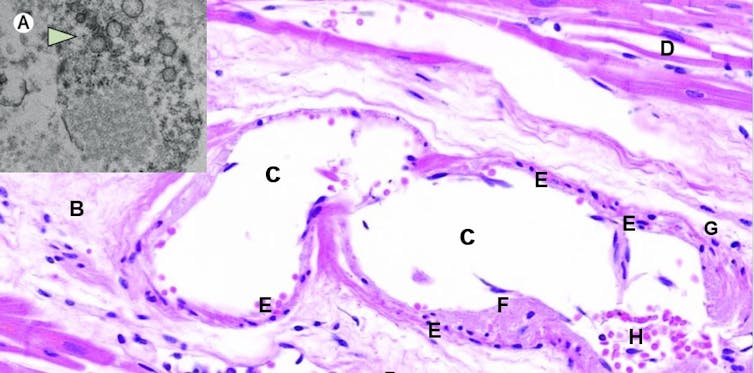

Otros estudios publicados con posterioridad realizados con pacientes holandeses, italianos y estadounidenses confirmaron lo que los médicos de todo el mundo ya sospechaban: uno de los marcadores de mal pronóstico en la COVID-19 eran los análisis que detectaban la formación de trombos (Figura 1).

Tanto las células epiteliales de los alvéolos pulmonares (neumocitos) como los endotelios vasculares disponen de receptores ACE2 en abundancia. Este receptor es la cerradura que encaja a la perfección con la proteína espiculada del virus, de forma que estas células abren sus puertas de par en par a la entrada del coronavirus, lo que provoca una endotelitis, es decir, una inflamación del endotelio vascular (Figura 3).